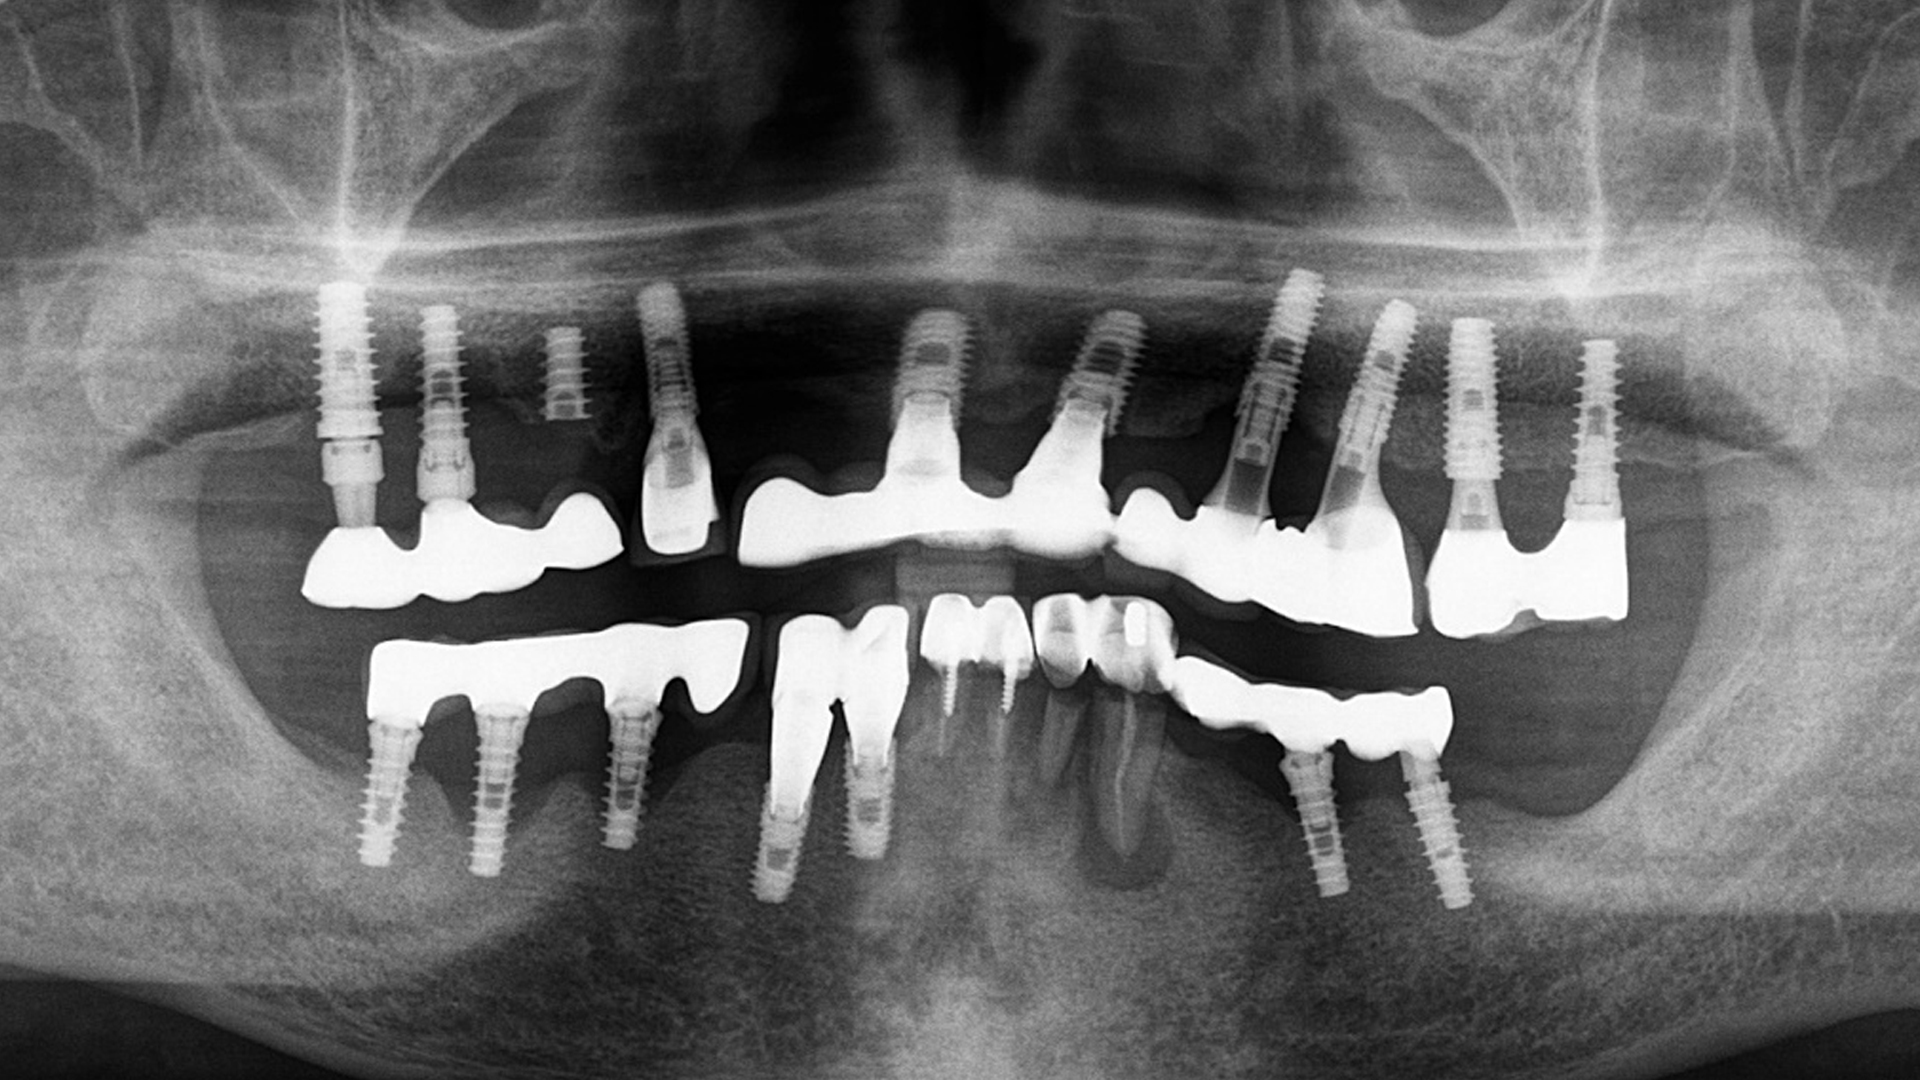

어렵다는 소리를 들은 고난도 임플란트

수명이 다한 임플란트의 재수술

임플란트가 대중화된 시대, 하지만 세월이 지나면서 부러지거나 염증이 생긴 임플란트들이 늘어나고 있습니다. 이런 경우 처치하기가 매우 어려워 많은 치과에서 포기하는 경우가 많습니다.

하지만 조현우 원장은 다릅니다. 치료 계획부터 임플란트 보철물 제거, 치조골 재건, 임플란트의 재식립, 저작기능 회복 후의 위생 관리까지 처음부터 끝까지 완벽하게 해결해드립니다.

"임플란트 재수술로 고민이신 분들"